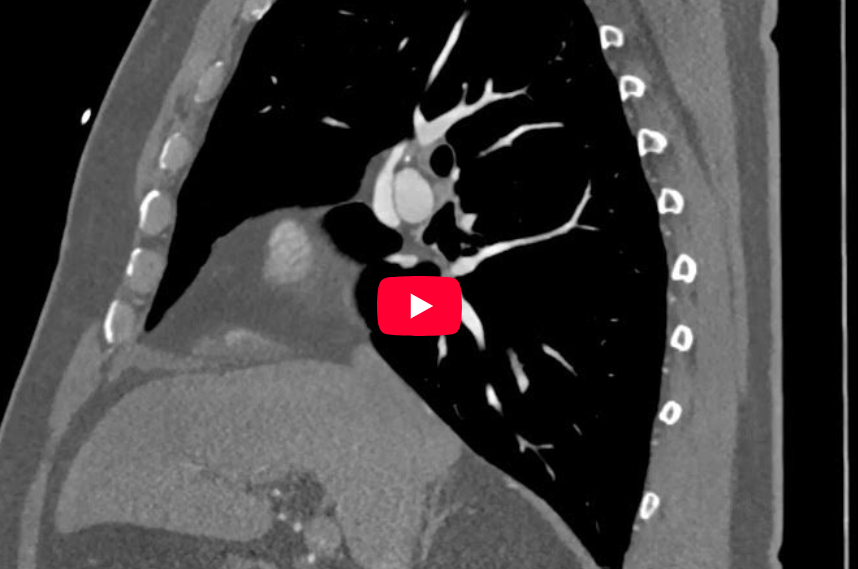

CAZ nr 112: Drenaj venos cardiac prin persistența de venă cava superioară stângă – variantă anatomică.

Video 1: reconstrucție axială a achiziției angioCT toracică cu sincronizare ECG

Video 2: reconstrucție sagitală a achiziției angioCT toracică cu sincronizare ECG

Video 3: reconstrucție coronală a achiziției angioCT toracică cu sincronizare ECG

Discuţie caz nr 112: drenajul venos cardiac nu este un subiect discutat în mod obișnuit deoarece variantele de drenaj venos nu implică boală cardiacă. În cele mai multe cazuri, drenajul venos cardiac este realizat de marea venă cardiacă care se deschide în atriul drept prin sinusul coronar. În acest caz, sângele venos cardiac este drenat superior prin persistența de venă cava superioară stânga în trunchiul venos brahiocefalic stâng, fiind variantă anatomică de drenaj venos cardiac.

DE LUAT ACASĂ!!! Variantele anatomice de drenaj venos cardiac sunt importante la pacienții la care se face planificarea pentru resincronizare cardiacă în echipa radiolog – cardiolog interventionist – aritmolog.